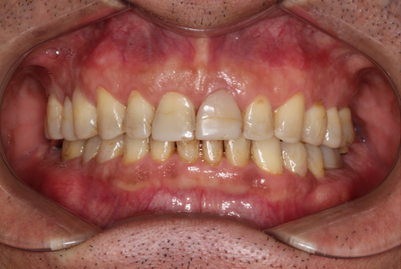

Mr NK, a 52-year-old male, presented with concerns of gradually shortening teeth and sensitivity to cold drinks. He also reported feeling self-conscious about his smile in photos. He is medically fit and has been using a night guard for his sleep-related grinding habit for the past year. Clinical examination revealed moderately worn dentition from erosion and attrition, along with mild crowding of the lower anterior incisors.

Intra-Oral Pictures (Before)

- Erosion severity: ACE Class Class III

- Reduced occlusal vertical dimension

- Mild crowding of lower anterior teeth